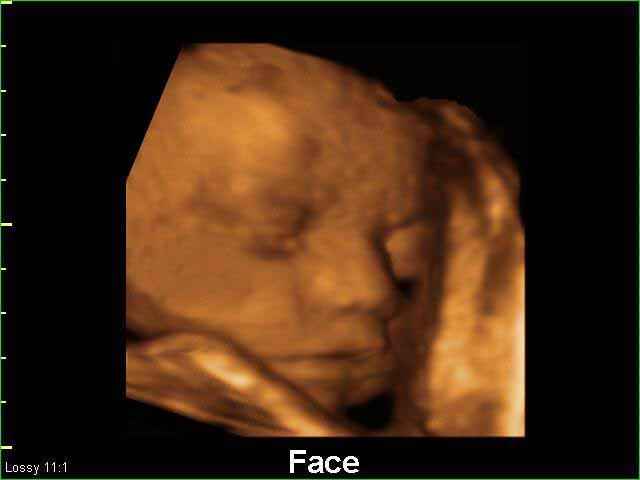

- Fetal Face Ultrasound Photos

3D Fetal Face Ultrasound Scan Photos | Dr N Layyous